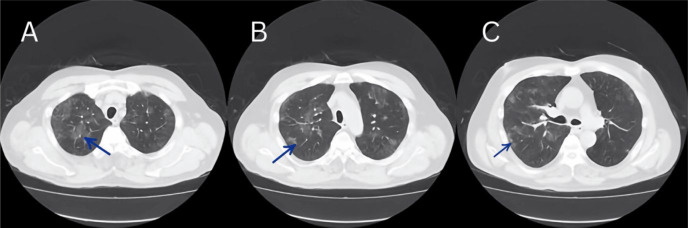

Hypersensitivity Pneumonitis (HP) is an allergic interstitial lung disease that arises from type III and IV allergic reactions. During the COVID-19 outbreak, HP was established as having similar manifestations to COVID-19. In remote rural regions of Japan, where respiratory specialists are not readily accessible, HP is not always easy to differentiate, and establishing a definitive diagnosis can be challenging due to insufficient laboratory examinations. Herein, we present a case of a moderately definite diagnosis of acute non-fibrosing HP. The foundation of treatment included antigen avoidance, which necessitates a comprehensive analysis of the patient's medical history. In instances where anomalous chest imaging outcomes are observed, it is imperative to conduct a comprehensive review of the patient's medical history, and to consider the possibility of HP.